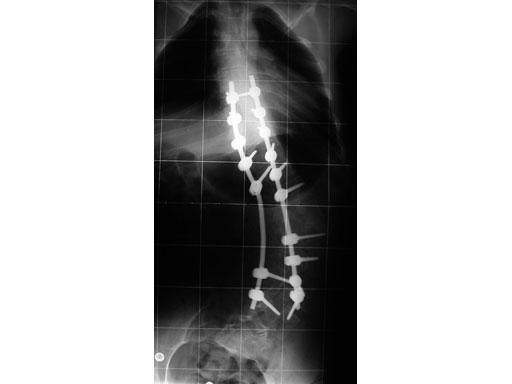

Case provided by Cornelius Wimmer, Vogtareuth, Germany

A 23-year-old man with neurogenic kyphoscoliosis, Cobb angle: 120. Fusion of T7S1 with universal reduction screws. Duration of surgery: 4.5 hours.